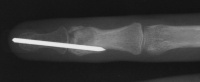

| Case 3. This 26 year old

woman presented with recurrent pain and swelling two years following

excision of an osteoid osteoma of the ring finger middle phalanx head.

Bone scan shows intense activity in this area, consistent with either

| The tumor was resected

using a dorsal tendon splitting exposure. |

| Debridement was continued

until normal counts were demonstrated . This left a thin

cortical shell which was reconstructed with a corticocancellous graft

from the distal radius. |